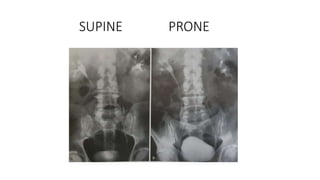

Prone film

• Better visualisation of distal ureters

• Lesions on anterior bladder wall well seen

• Bladder hernias well seen

Rationale of a prone film:

Contrast is denser

• Upper pole is posterior than the lower pole in supine position and so,

drainage is hindered. In prone, it is reversed

• Ureters are anterior to renal pelvic plane in supine position and in prone, it

is reversed

SUPINE PRONE